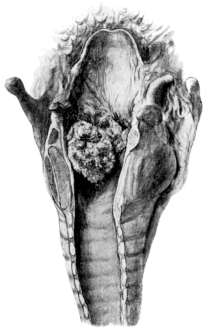

| 256. | Multiple Papillomata of the Larynx | 479 |

| 259. | Intrinsic Tumour of the Larynx | 487 |

| 260. | Extrinsic Tumour of the Larynx | 487 |